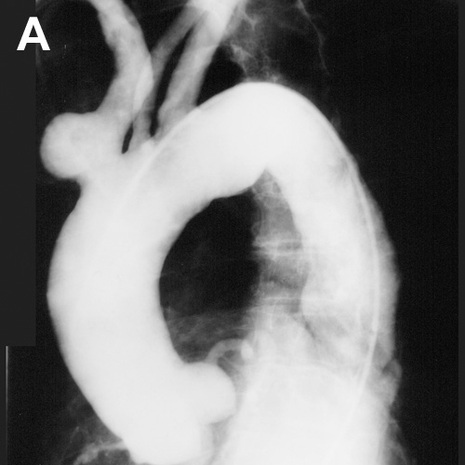

Image A shows an abnormality of the branches off the aorta:

The aorta is outlined in red.  The first branch, the brachiocephalic artery, is shown in green.  There is a rounded outpouching near the origin of this vessel that protrudes from the anterior side of the vessel.  A contour abnormality of this type is called a saccular aneurysm, and in this patient this abnormality was visible on the lateral chest radiograph, simulating an anterior mediastinal mass.  The normal left common carotid artery is shown in yellow and the normal left subclavian artery is shown in blue.